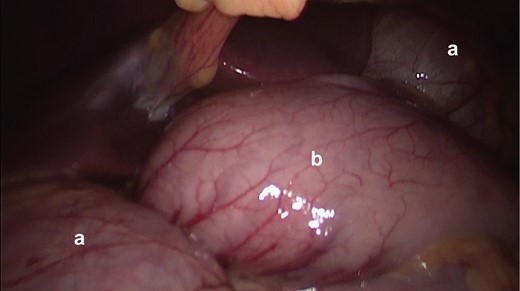

Initial picture in diagnostic laparoscopy. It is seen that the herniated colon (a), through the foramen of Winslow and the stomach (b).